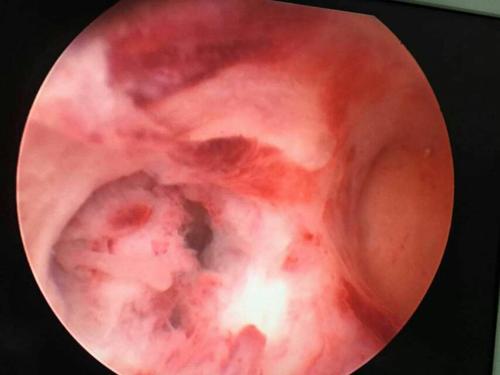

宫腔粘连图片宫腔镜

宫腔粘连图片宫腔镜,宫腔粘连严重图片

【病例分享一】宫腔镜宫腔粘连电切术

宫腔粘连

宫腔粘连严重图片

重度宫腔粘连图片